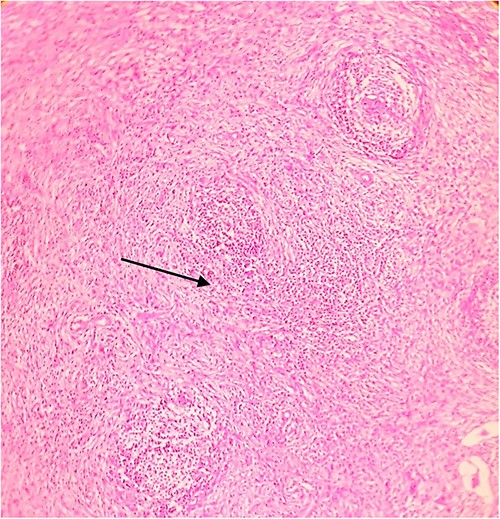

Postoperative histopathology H&E stain: 10× magnification of a representative perigastric lymph node showing tumour (arrow head) surrounding the germinal centres (arrow).